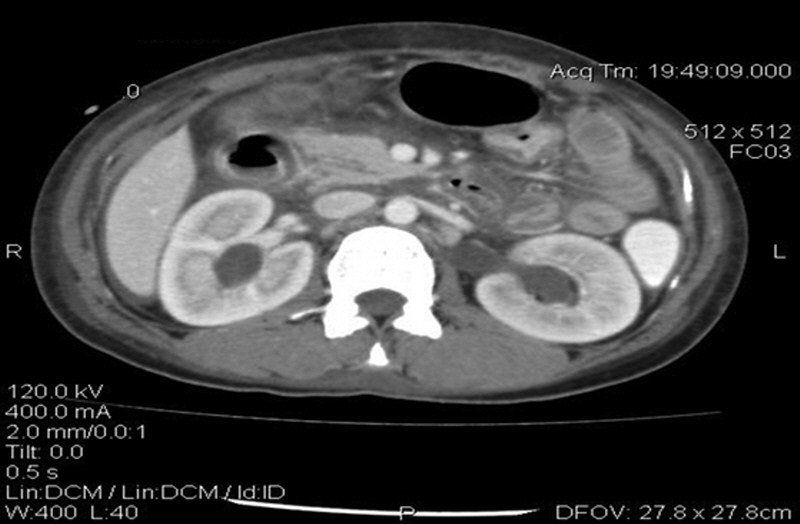

癌胚抗原(CEA)水平正常,但CA-125水平升高为93.5μg/ml(正常范围,0~35μg/ml)。进行腹部和盆腔的CT扫描,证实存在中度腹水和腹膜结节(图2)。膀胱壁和肠壁增厚(图3)。双侧肾积水和多个扩大的主动脉旁淋巴结也可见(图4)。

图4 腹部增强CT显示双侧肾积水

泌尿生殖系统的临床表现比较少见,往往与胃肠道疾病相关。狼疮性膀胱炎的发病机制是免疫复合物介导的血管炎。由此产生的慢性炎症和泌尿系统运动障碍导致膀胱壁增厚、泌尿系统梗阻性疾病和肾积水。本例患者双侧肾积水,超声和CT扫描显示膀胱壁增厚,后来在膀胱镜检查中证实。这些是SLE最常见的泌尿系统表现和血管炎现象。